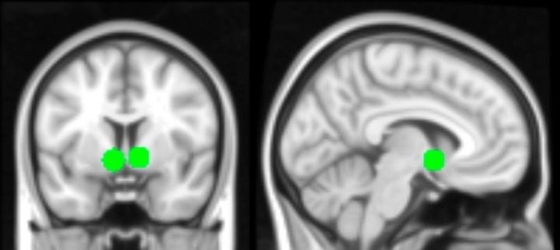

A képek érdekessége az volt, hogy a fotók alatt a Facebook rendszeréhez hasonlóan megjelent a lájkok száma is, erre pedig a gyermekek azt hitték, hogy azok az ismerőseiktől származnak (ehelyett maguk a kutatók adtak véletlenszerű értékeket). Meglepő, de akkor amikor az MRI-vizsgálat során megjelent a fiatalok saját képe az arra kapott lájkok számával, akkor az agy több területe is aktiválódott, köztük a jutalmazásért felelős rész is.

Ez gyakorlatilag azt jelenti, hogy az ember pontosan ugyanazt éli át, mint amikor jó jegyet kap az iskolában, vagy épp megjutalmazza magát egy finom édességgel. Szintén izgalmas, hogy amikor a kutatók rákérdeztek, hogy a diákok lájkolnák-e az előttük megjelenő képet, a többség annak fényében döntött, hogy azon hány lájk volt. Ez azt jelenti, hogy a népszerű emberek képei még népszerűbbek lesznek, míg az egyébként jó tartalom egy népszerűtlen fiatalnál könnyen észrevétlen marad.